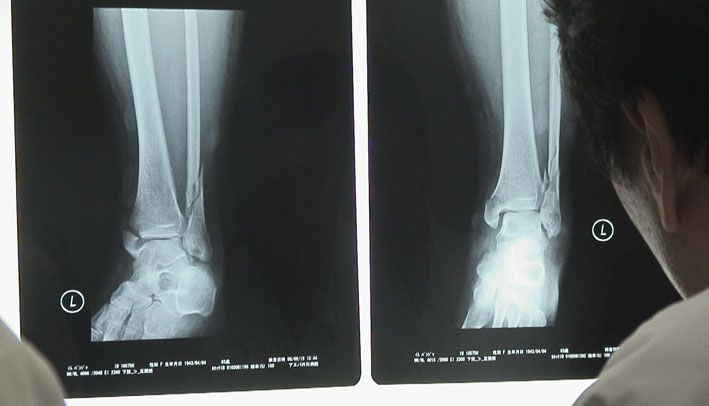

レントゲン写真にみる骨折のもよう。

いい景色を見て下りるとき、バンジャは足を滑らし、骨折のケガをした。

すぐ、延吉にある延辺大学病院で、診察をしてもらった。レントゲンを撮ってみると足の骨が折れていた。